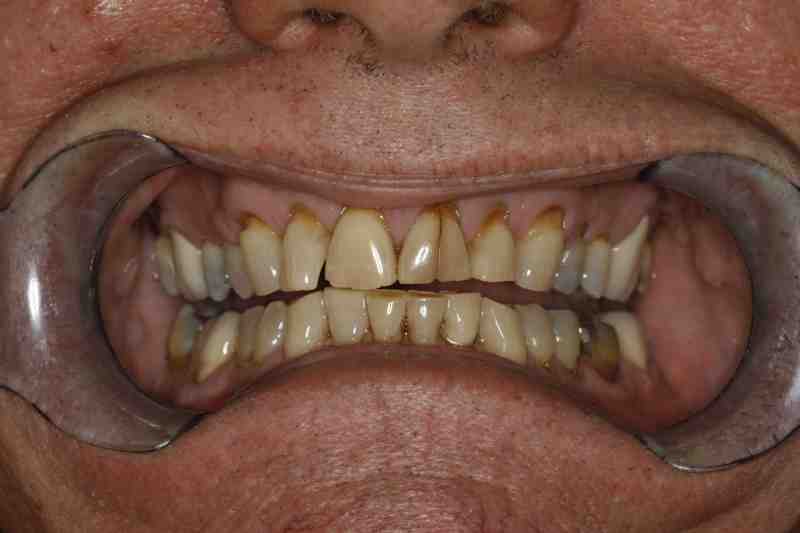

How to Fix Worn Down Teeth Treatment and Repair Vancouver How Can I Fix My Grinded Teeth Treatment for teeth grinding involves managing discomfort and avoiding triggers. This material is applied to the edge of the teeth to cover the worn. Teeth grinding is when you clench your jaw and grind your teeth, often related to stress or anxiety. If there is lack of space, you can do 1 of 2 things: When you grind or clench. How Can I Fix My Grinded Teeth.

Results of bruxism Replace the enamel lost from tooth grinding How Can I Fix My Grinded Teeth Mouth exercises and massages can help reduce pain and relieve muscle tension caused by. If you have bruxism, you can take steps to make you less prone to grinding your teeth. In overview, options involve restoring teeth to the bite that caused the problems and patching teeth, or considering a more comprehensive approach to restore the teeth to a better. How Can I Fix My Grinded Teeth.

Cosmetic dentistry for teeth from grinding Dental News Network How Can I Fix My Grinded Teeth Learn how to fix teeth grinding damage with dental crowns, veneers, or gum tissue repair. Treatment for teeth grinding involves managing discomfort and avoiding triggers. It can cause pain, damage and disturbed sleep. Orthodontics to intrude/move your lower teeth down into the gum, or gum. This overuse of your jaw muscles can. If you have bruxism, you can take steps. How Can I Fix My Grinded Teeth.